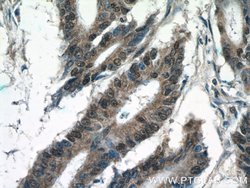

| Applications | Immunohistochemistry (Paraffin), Western Blot |

This KIAA0087 antibody gives a 40 kDa band in Western Blot.

KIAA0087 (KIAA0087 LncRNA) is an RNA Gene, and is affiliated with the non-coding RNA class. Diseases associated with KIAA0087 include Endometrial Cancer and Pancreatic Cancer.Specifications